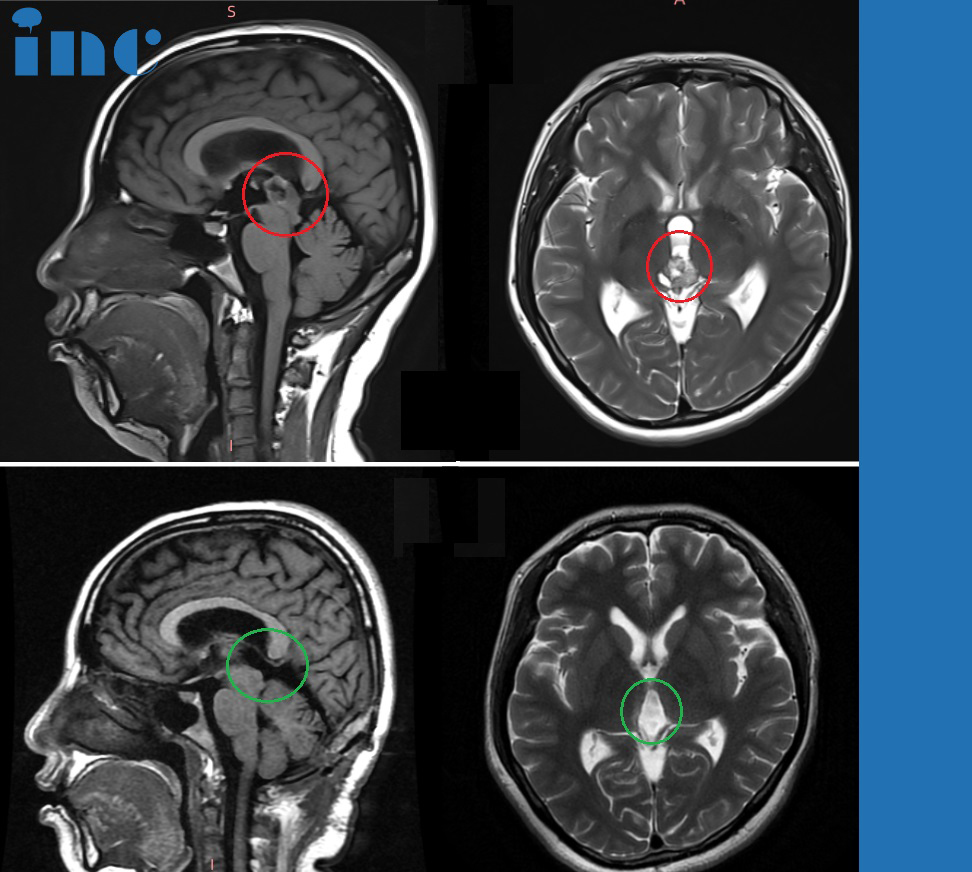

巴特朗菲教授北京天壇醫(yī)院手術(shù)案例

巴特朗菲教授北京天壇醫(yī)院術(shù)后